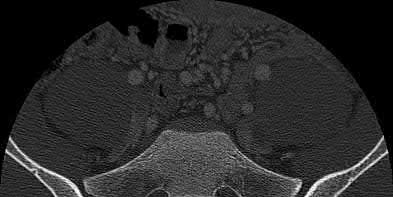

Which of the following images shows an injury pattern most consistent with a lateral compression type 3 pelvic ring injury?

Figure C is an axial CT scan of a lateral compression type 3 (LC3) pelvic ring injury.

Classically, LC3 injuries demonstrate an ipsilateral lateral compression and a contralateral APC (windswept pelvis) fracture pattern. The most common mechanism of injury in these cases is a rollover MVC or pedestrian vs. auto. LC1 injuries are characterized by an oblique or transverse ramus fracture and ipsilateral anterior sacral ala compression fracture, while LC2 injuries consist of a rami fracture and ipsilateral posterior ilium fracture dislocation (crescent fracture). While LC1 injuries can often initially be managed conservatively with protected weight-bearing and close observation, LC2 and LC3 pelvic ring injuries are almost universally operative.

Pennal et al. discuss a radiologic technique for assessing the forces producing pelvic disruption and its use in logically classifying pelvic injury. Based on this radiologic assessment and along with some biomechanical studies, they propose a classification system involving three major forces producing injury that can also be helpful in the management of these patients.

Young et al. performed a retrospective analysis of the plain radiographs of 142 cases of pelvic fractures and identified four patterns of force that presented with distinctive, recognizable radiographic appearances. They describe a classification system for pelvic fractures based on radiographic and clinical findings that correlates with associated injury to soft-tissue structures and enables the surgeon to begin corrective procedures rapidly.

Incorrect Answers:

Answer 1: This represents a lateral compression type 2 injury. Answer 2: This represents a lateral compression type 1 injury.

Answer 4: This represents an anterior posterior compression type 2 injury. Answer 5: This represents an anterior posterior compression type 3 injury.